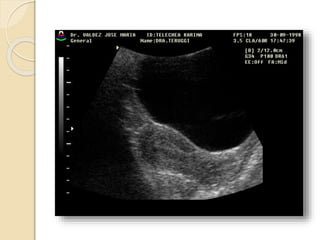

Ecografia tocoginecologica